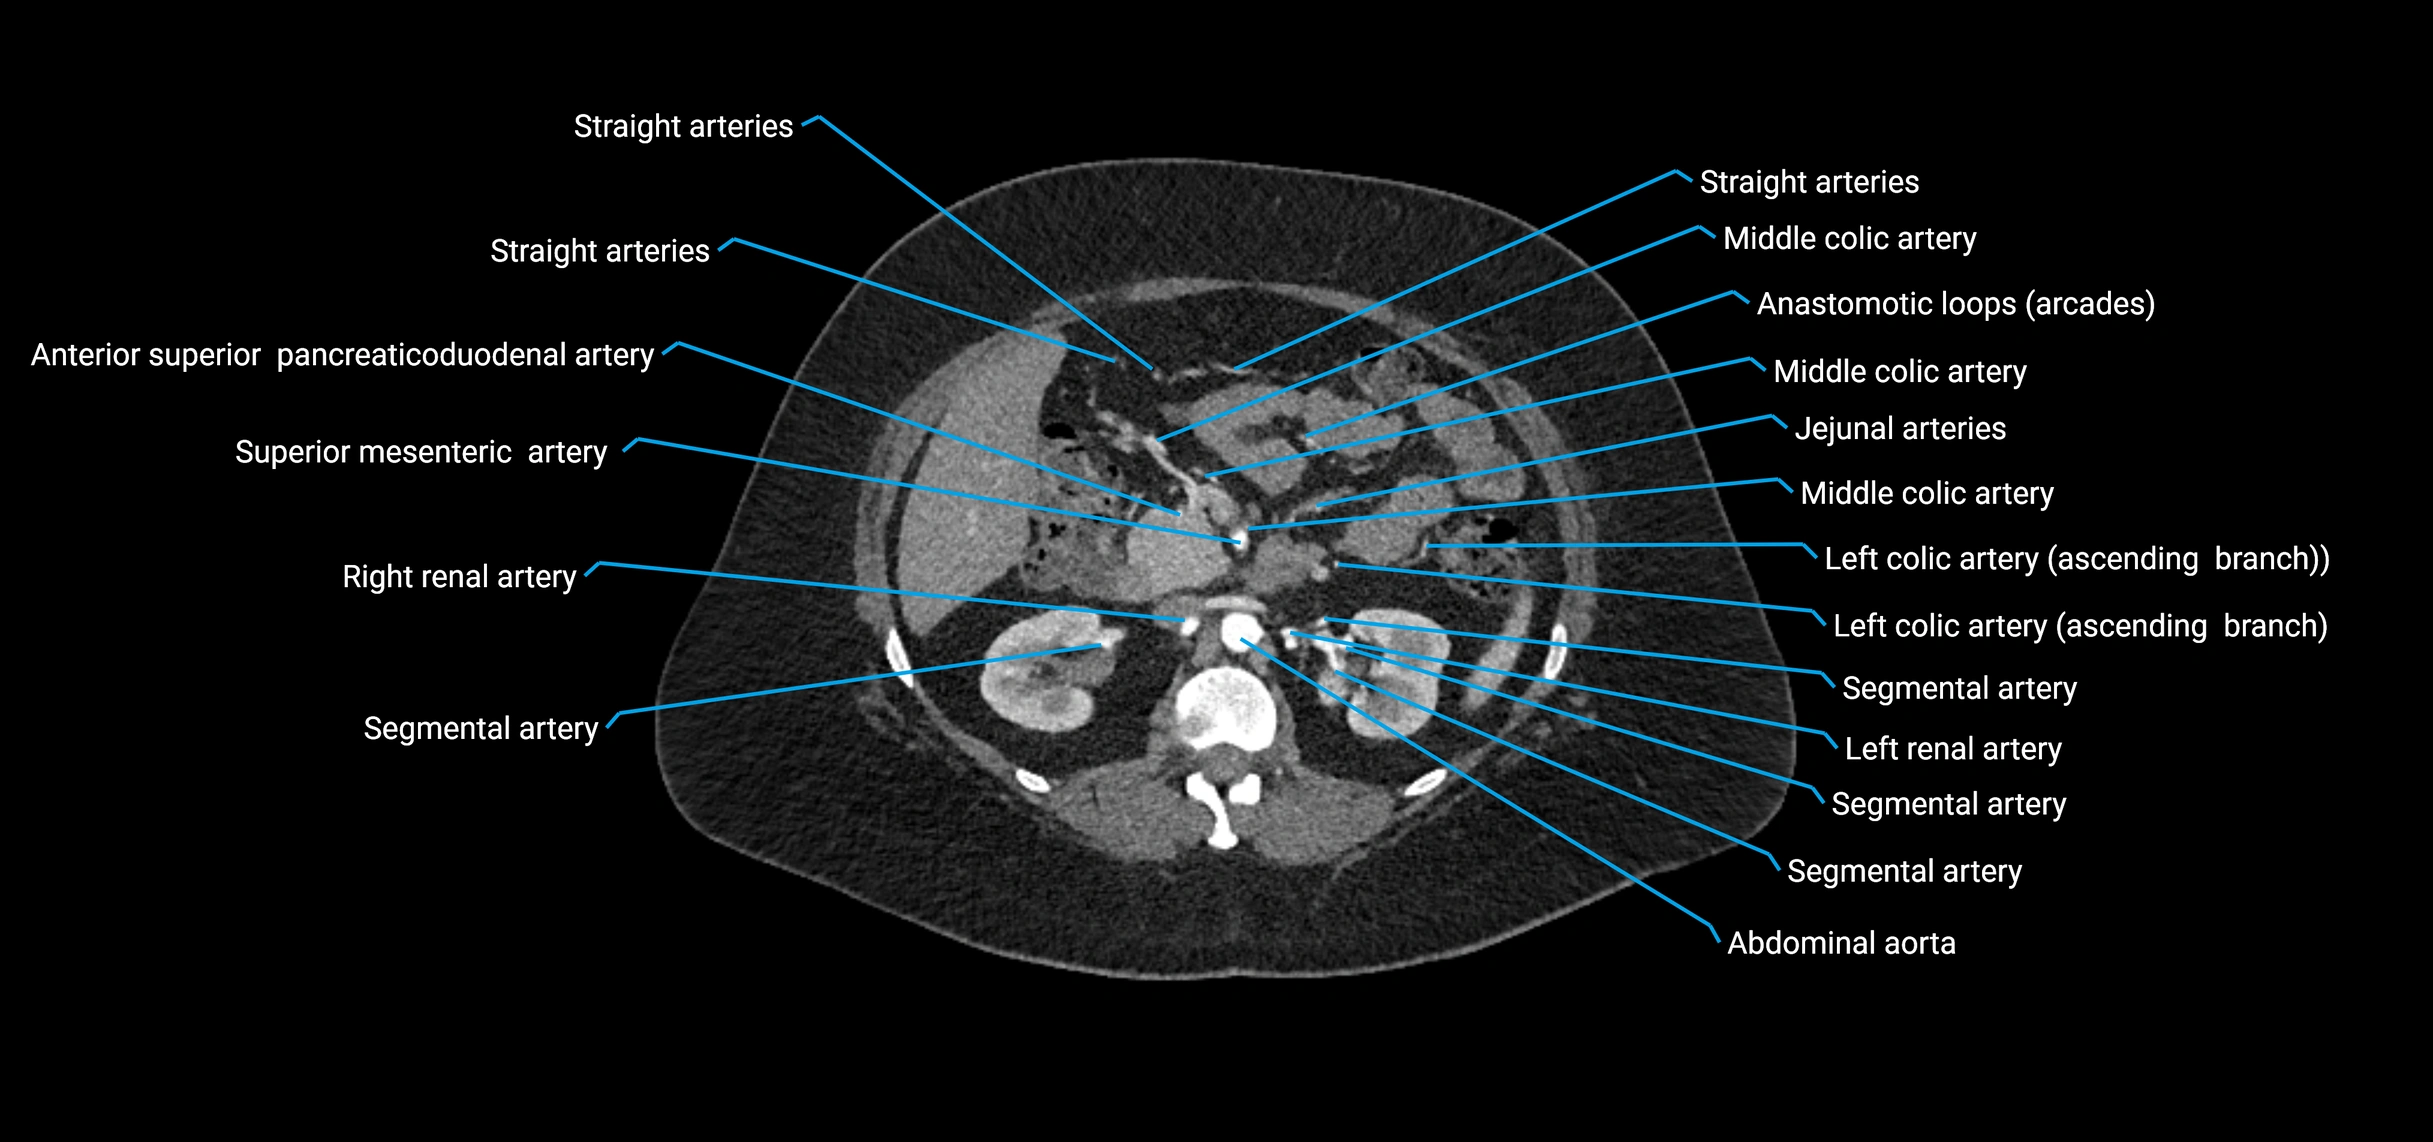

Contrast-enhanced CT (CTA):

• Gold standard for abdominal aortic imaging

• Provides excellent detail of lumen, wall, aneurysm, thrombus, and branch vessels

• Multiplanar and 3D reconstructions help in aneurysm measurement, stent graft planning, and dissection evaluation